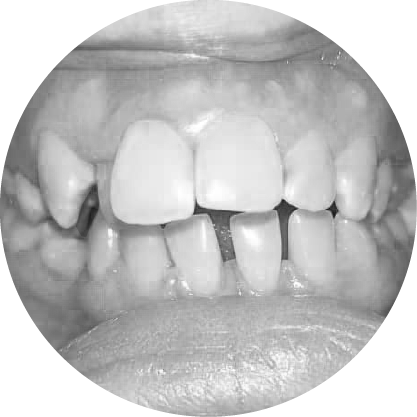

ตัวอย่างในชีวิตจริง